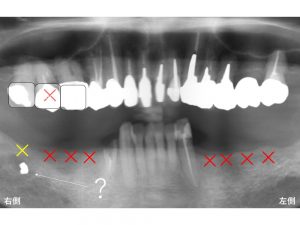

ちなみに下顎の右側の親知らず付近に骨の中に白ぽいものが写っています。

これって何なのでしょうか?

これは多分金属です。

過去の治療の中で何かの問題があり、

金属が折れて骨の中に残っているのでしょう。

患者さんご自身も過去の治療のことで覚えていませんでした。

我々の所に初診時にご来院された時にはすでにこの状態でしたので

骨の中にレントゲンで白く見える物が何かは正しくは判断できません。

しかし、現在痛みもなければ、腫れもしないのでこのまま経過観察することにしました。